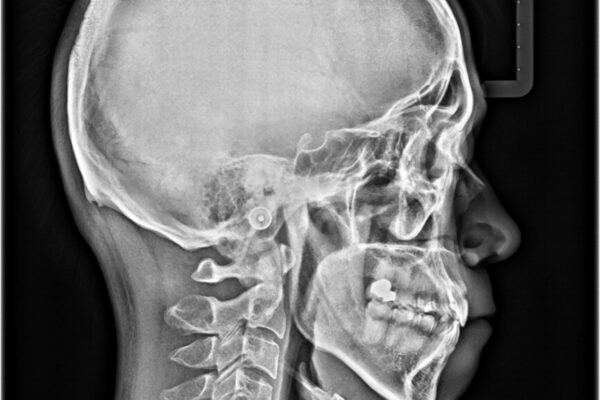

「八重歯を治したい」とご相談いただいた患者様の症例をご紹介します。

上下の前歯部に強い叢生(ガタガタの歯並び)があり、そのまま歯を並べると出っ歯になってしまう可能性がありました。

そこで、上下左右の第一小臼歯を抜歯し、歯が並ぶためのスペースを確保し叢生を解消する治療計画を立てました。

八重歯はきれいに整い、前歯もバランスよく収まり、横顔のラインも自然に改善されました。